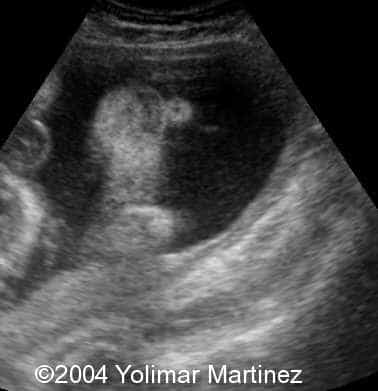

Microophthalmia and hypotelorism

Imagen 38